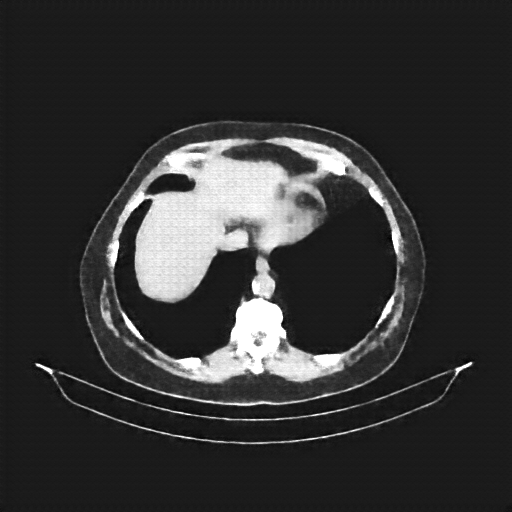

Original NATIVE CT scan (input)

Full window (WL 1023.5, WW 4095 β†’ Low βˆ’1024, High +3071)

Actual HU range: [-160.0, 240.0]

Lung window (WL -600, WW 1500 β†’ Low βˆ’1350, High +150)

Actual HU range: [-160.0, 150.0]

Mediastinum window (WL 40, WW 400 β†’ Low βˆ’160, High +240)